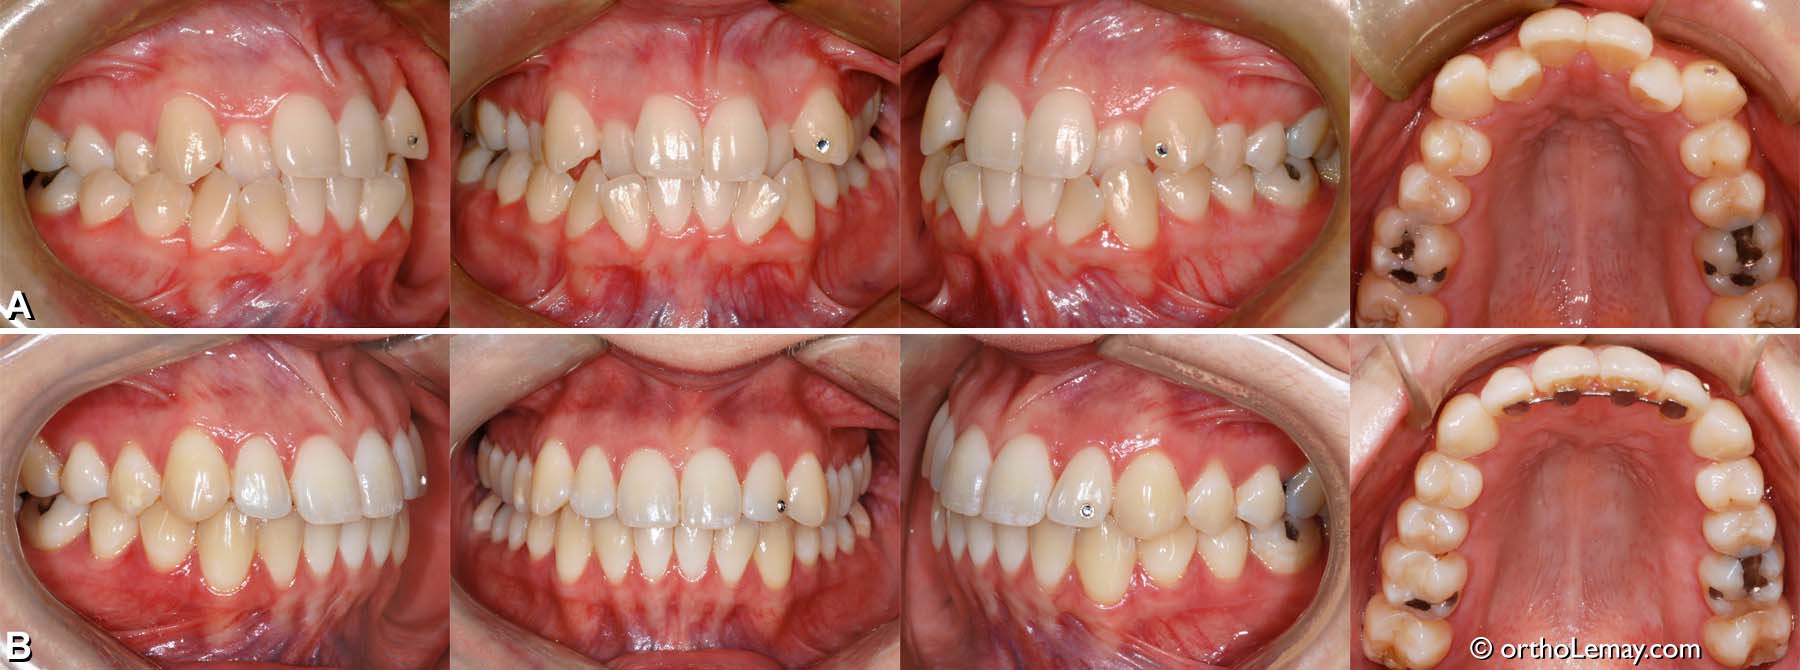

Exemple de traitement de malocclusion classe 1 (14)

(A) Adulte de 24 ans avec déficience maxillaire modérée (arcade supérieure étroite), linguo-version des latérales supérieures manque d’espace important aux deux arcades et interférences fonctionnelles.

(B) 4 ans après la fin du traitement d’orthodontie, l’occlusion est très stable. On note une très légère récession gingivale sur les premières prémolaires supérieures qui était présente à la fin du traitement, mais qui est demeurée stable depuis ce temps. Le point argent sur une dent avant (canine) et après (latérale) le traitement est un “diamant” esthétique que la patiente s’est fait coller sur la dent.